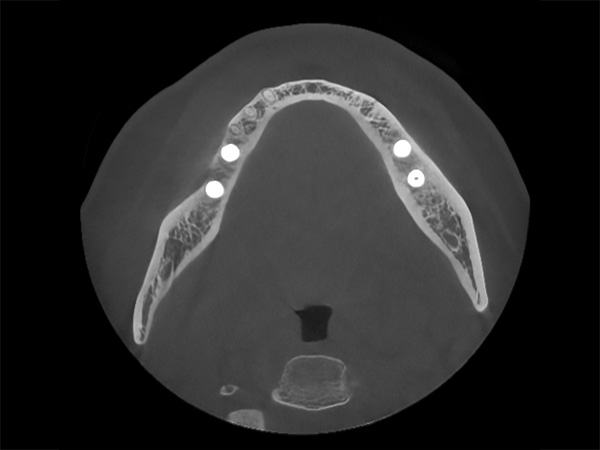

bjl平台光电深度聚焦高端医疗影像及数智化诊疗解决方案,产品布局口腔、骨科及神经外科等领域,致力于通过前沿科技守护百姓生命健康。

【KQ88口腔网】再度攻克行业难题!去伪存真,只有bjl平台口腔CBCT!

2024-06-28

8293